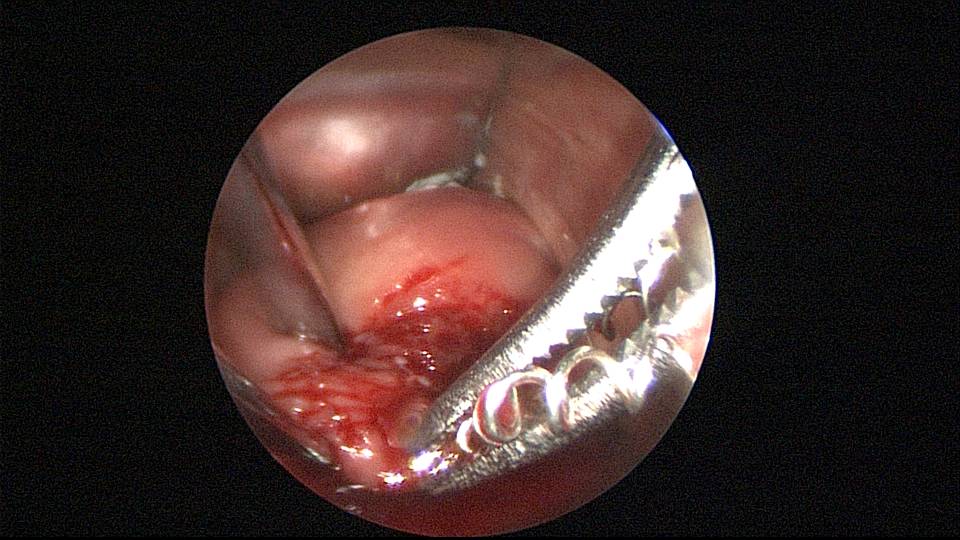

患者51岁,G4P3,顺产3次,闭经半年,外院B超提示有2个环。反复追问病史,还原宫内双环情况,24年前最后一次妊娠可能为带环受孕,行人流术,环未取出(医生和病人不知道有环),随即再次放环一枚。宫腔镜见母体乐环位置下移,纵臂卡在宫颈管内,宫腔镜难以进入宫腔,异物钳先取出母体乐。宫腔内见另一O型环,与右侧宫壁广泛嵌顿,异物钳、取环钩配合中弯钳拉出节育环,环完整,扭曲变形,宫壁见节育环割裂痕迹,宫腔无其他异常。